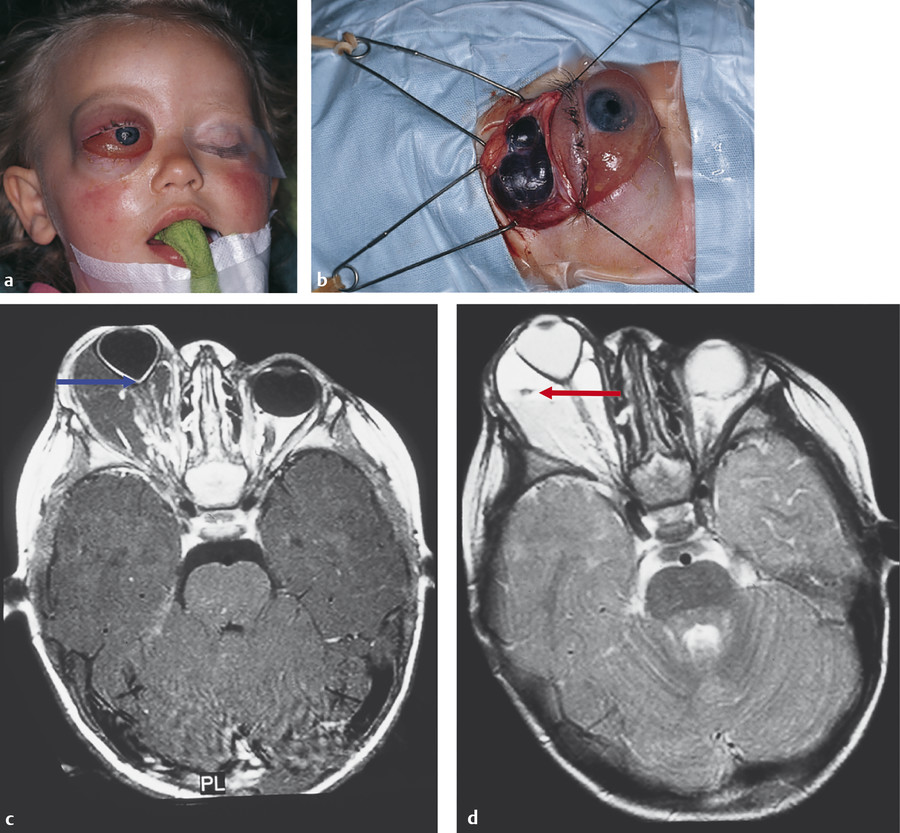

It is important to be aware that orbital disease occurring in childhood has little overlap with that occurring in adulthood, although the approach to patient evaluation is very similar. Orbital cellulitis is the most commonly encountered orbital disorder of childhood. Malignant tumors, including rhabdomyosarcoma and neuroblastoma, are very rare, but rhabdomyosarcoma must be considered in any child presenting with a rapidly progressive orbital or eyelid mass and proptosis. Choristomas, such as dermoid cysts, and hamartomas, such as capillary hemangiomas, are the most common orbital lesions encountered in childhood. In contrast to adulthood, thyroid eye disease is very rarely encountered in childhood.

Rhabdomyosarcoma must be considered in any child presenting with a rapidly progressive proptosis or orbital or eyelid mass.